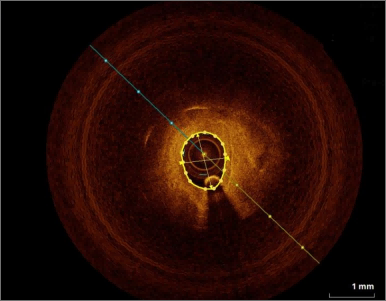

埃斯科核心实验室(IsCore image corelab) 是晓得(北京)商业发展有限公司旗下 的独立第三方核心实验室。由经验丰富的临床专家团队和影像放射专家团队组成, 致力于帮助临床医生和医疗领域的公司进行细致的、标准的、规范的影像管理和 判读。IsCore 影像实验室提供的影像判读数据已经为多家医疗机构的科研课题提 供数据支持,同时也已经协助国内外数个产品研发上市提供科学帮助。我们实验室的影像评价者均在国内顶尖专科医院接受过临床影像专业的系统学 习与规范培训,有多年的临床工作经验,以及强大的技术支持,能准确判读 MRI, HRMRI, DSA, OCT, CFD, VU 等影像,给出标准规范的报告结果,最低限度减少 了人为因素对试验结果的影响有助于科研成果产出和产品研发。